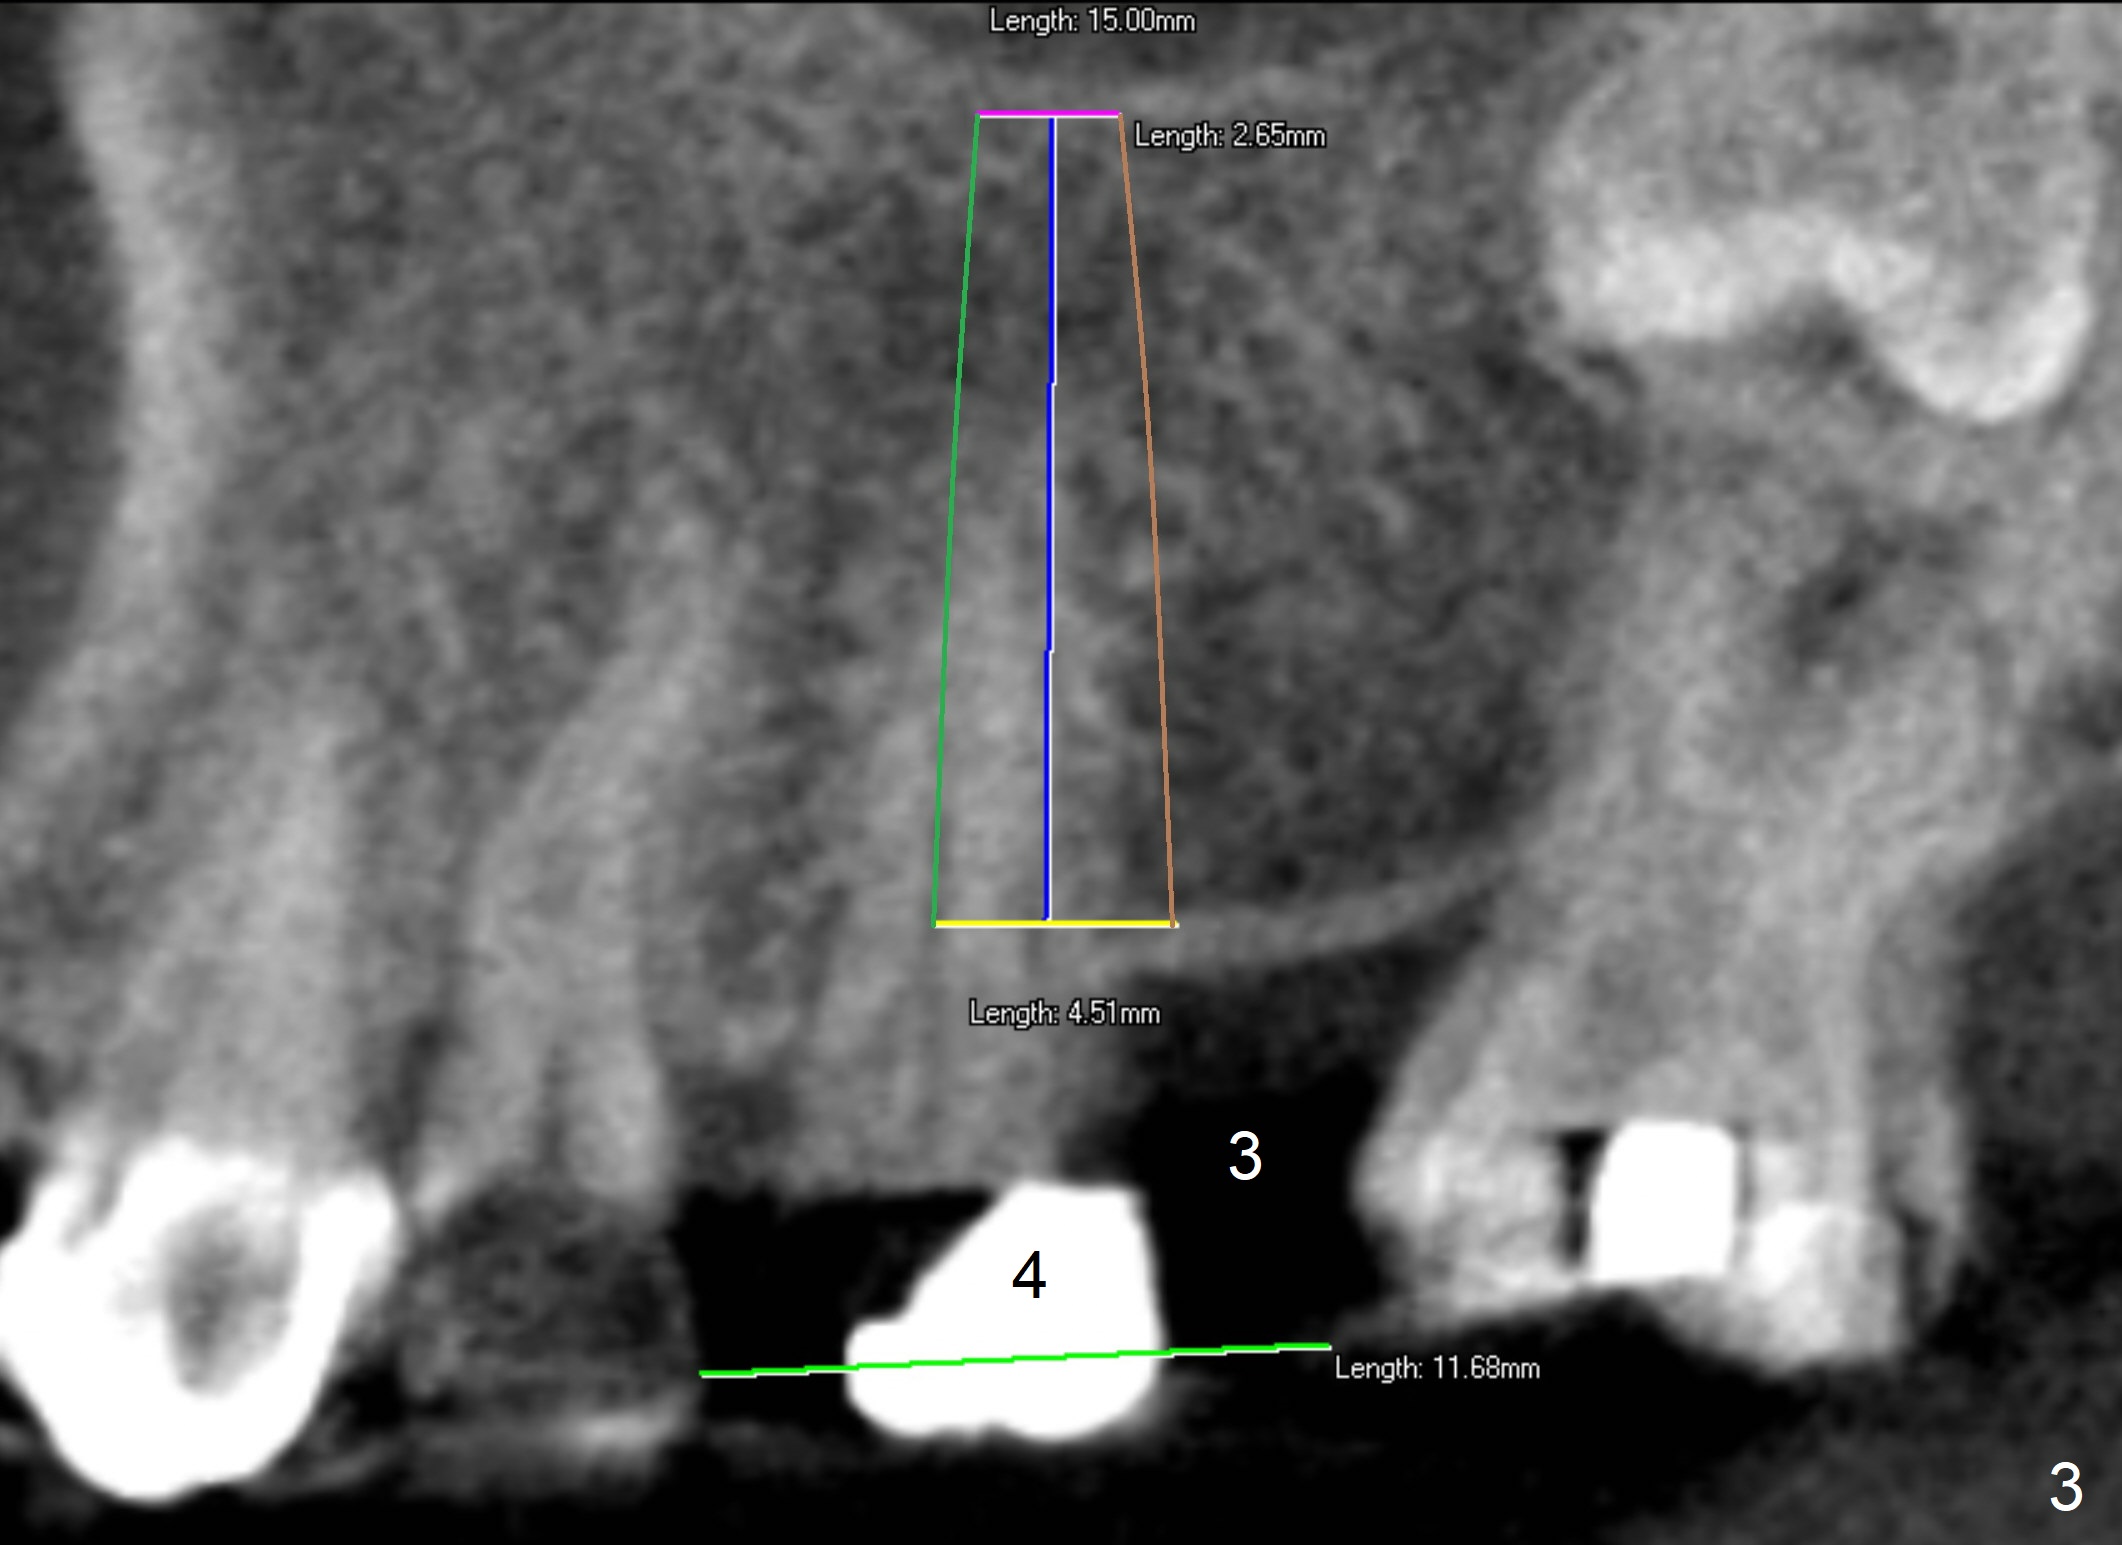

A 62-year-old man has sudden severe pain associated with the tooth #4. Since the edentulous space at #3 is narrow (Fig.1,3), an implant is placed distal to the site of #4 (after extraction) as a molar (Fig.2-4). Use Lindamann bur to remove the bone in the distal wall of the socket prior to osteotomy (Fig.2 red dashed area).